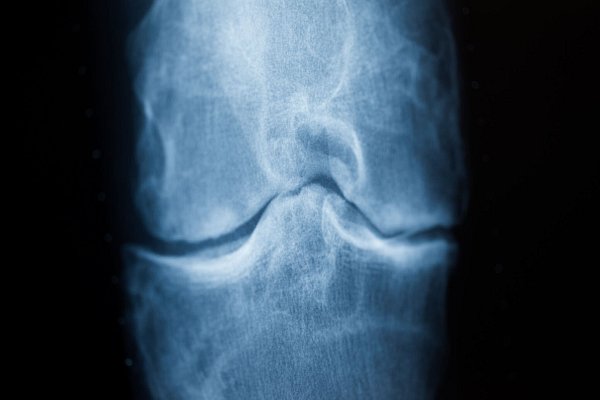

Spätestens das Röntgenbild schafft Klarheit: Der Knorpel nutzt sich immer mehr ab. Im späteren Stadium einer Arthrose reibt Knochen direkt auf Knochen. (Archivbild) - © Rolf Vennenbernd/dpa/dpa-tmn

Spätestens das Röntgenbild schafft Klarheit: Der Knorpel nutzt sich immer mehr ab. Im späteren Stadium einer Arthrose reibt Knochen direkt auf Knochen. (Archivbild) | © Rolf Vennenbernd/dpa/dpa-tmn